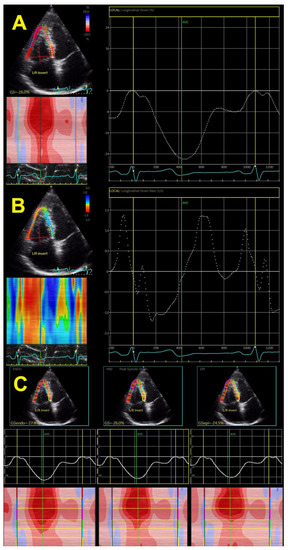

The speckle tracking-derived RV longitudinal strain has been the only method used in the last decade (Figure 3A), whereas the tissue-Doppler-derived strain has not been used for evaluation for a long time due to many limitations. This technique also provides a calculation of strain rates (systolic, early, and late diastolic strain rates) (Figure 3B), which is the speckle tracking equivalent to parameters obtained by tissue Doppler, giving data on systole and early and late diastole. Novel echocardiographic methods enable the assessment of epicardial and endocardial RV longitudinal strain rates (Figure 3C), which has also been used in the hypertensive population.

Figure 3.

Two-dimensional global right ventricular strain (A), right ventricular strain rate (B), and layer-specific strain—endocardial, mid-myocardial, and epicardial (C).

Early findings revealed that the free wall RV longitudinal strain was gradually reduced with systolic BP [27]. The same was reported for the early diastolic strain rate but not for late diastolic and systolic strain rates. Our study group showed that RV GLS and, particularly, free wall RV longitudinal strain were deteriorated in patients with different forms of hypertension, such as white-coat hypertension, masked hypertension, and nocturnal hypertension, but also in patients with high-normal BP [21,33,34,35,36]. Patients with unfavorable circadian BP patterns (non-dipping and reverse dipping) also have significantly lower values of RV longitudinal strain in comparison with dipping and extreme dipping BP patterns [33]. RV GLS also gradually reduced from hypertensive patients with normal geometry and concentric remodeling, across those with eccentric and dilated LVH, to those with concentric and concentric-dilated LVH [28].

Patients with comorbidities such as obesity, diabetes, and metabolic syndrome had worse RV GLS than patients with isolated hypertension [36,37,38,39], which shows that comorbidities have both additive and cumulative negative effects on RV mechanics. Studies also revealed that the RV endocardial layer was more impacted by arterial hypertension than the epicardial layer in hypertensive patients; this was also found in hypertensive patients with diabetes and obesity [34] and patients with white-coat or masked hypertension [33,34]. Systolic BP correlates well with layer-specific RV longitudinal strain, independent of other clinical and echocardiographic parameters [33,34,38].